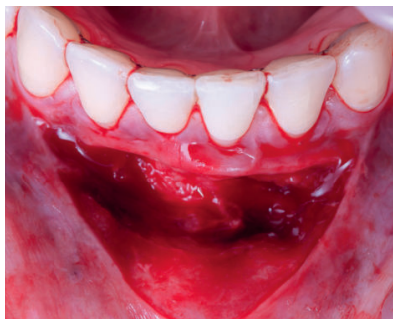

Previamente a la intervención, la paciente se enjuagó durante un minuto con un colutorio de clorhexidina. La técnica quirúrgica comenzó con la preparación del lecho receptor, se realizaron incisiones intrasulculares a nivel cervical hasta la línea ángulo de todos los dientes del frente antero-inferior (33-43), desinsertando la base de la papila sin seccionarla con la ayuda de instrumentos de tunelización. Posteriormente se realizó una incisión en el fondo de vestíbulo (Figura 11). A continuación, se obtuvo un injerto de tejido conectivo del paladar introduciéndolo en el lecho receptor, siendo todas las suturas realizadas de la misma manera que en el caso clínico 1, usando tanto material reabsorbible como no reabsorbible de 5/0 y 6/0 ceros (Figura 12).